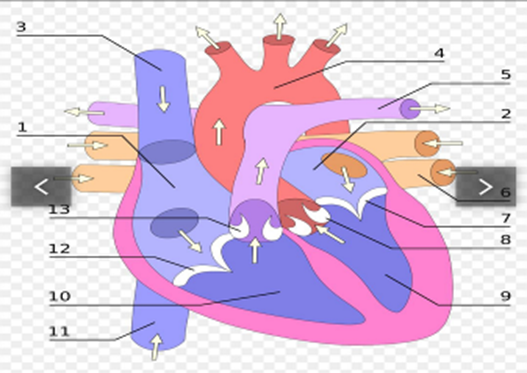

“O‘rnini top” didaktik o‘yini tashkil etiladi: doskaga yurakning yirik sxematik tasviri tushirilgan plakat ilib qo‘yiladi. O‘quvchilarga yurakning quyidagi anatomik tuzilmalari nomlari yozilgan yopishqoq kartochkalar tarqatiladi: o‘ng va chap bo‘lmachalar, o‘ng va chap qorinchalar, yuqori va pastki kovak venalar, aorta, chap o‘pka arteriyasi, o‘ng o‘pka venalari, ikki tavaqali (mitral) klapan, uch tavaqali (trikuspid) klapan hamda yarim oysimon klapanlar. O‘quvchilar navbat bilan doskaga chiqib, kartochkada ko‘rsatilgan yurak tuzilmasining anatomik jihatdan to‘g‘ri joylashuvini aniqlab, plakatga joylashtiradilar.